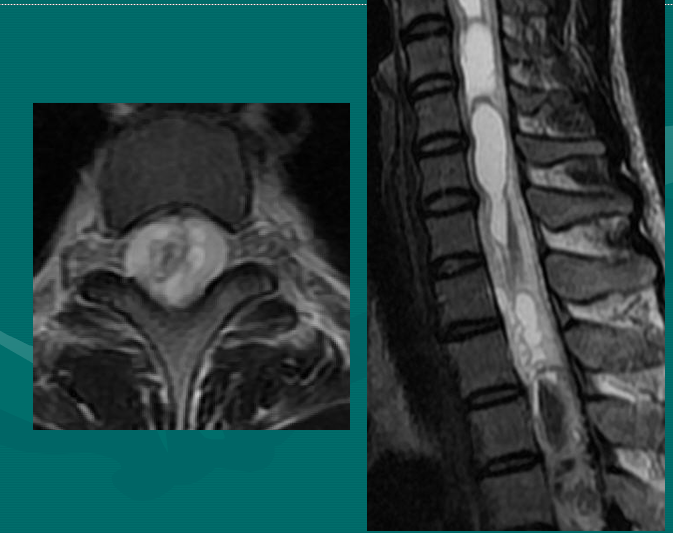

后纵韧带(PLL小蓝箭头)在图像中表现为沿着每个椎体及椎间盘后缘垂直向下的黑线。有意思的是,尽管此病人有一个9mm的椎间盘突出(HNP),骨质有一定的翘起,在椎间盘平面以上可见髓核物,但后纵韧带仍然包容着突出的髓核物而没有游离出。这种情况在学术上被称作一个大的包容性椎间盘突出。

硬膜囊(红星)表现为“超白色”结构,填充在椎体后方的中央椎管内。此囊袋内有可自由浮动的由运动神经纤椎及感觉神经纤维共同组成的脊神经根(马尾)。

黄韧带(绿星)位于每个椎骨之间,增强脊柱的稳定性。此结构可变大或增厚,助长年长者易患的中央型椎管狭窄的形成。

MRI表现

颈腰段椎管前后径:相对狭窄- 12~15mm绝对狭窄-小于10mm。